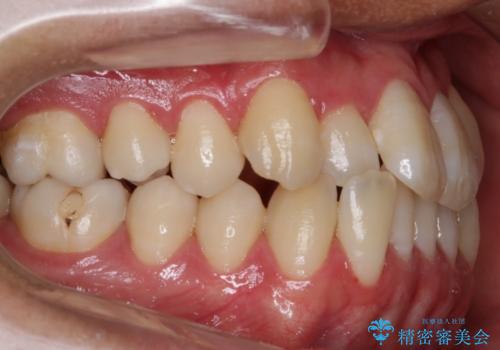

非抜歯での治療

抜歯をせずに歯のガタつきを治すためのスペースを作るために

①歯の遠心移動

②歯列弓の拡大

③IPR(歯を少し小さく削る)

この3つの方法を複合的に組み合わせて治療を行いました。

抜歯をせずとも笑った時の歯の見え方が劇的に変化していることが分かります。